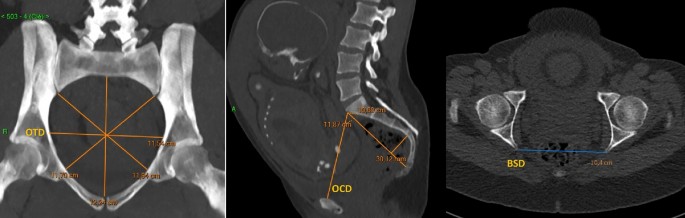

Pelvimetries were performed by a 64-channel CT scanner, in a supine position. CT-pelvimetry protocol consisted in a scout-view acquired with a current of 60 mA/s and a tube voltage of 120 kV, and a low-dose helical acquisition with the following parameters: peak tube voltage of 100 kV, tube current–time product of 20–25 mA/s, detector collimation of 16 × 1.2 mm, reconstructed in 3 mm sections using the C filter (corresponding to a moderately sharp reconstruction kernel), and iterative reconstruction (SAFIRE) with a pitch of 0.8 (Somatom Sensation®, Siemens Healthineers, Erlangen, Germany). The different obstetrical diameters of the pelvis were measured by multiplanar reconstruction using an image communication and archiving system (Carestream®, Carestream Health, Rochester, NY, USA), by radiologists from the University Medical Centres of Besançon and Toulouse. On the axial oblique view through the pelvic inlet and on the mid-sagittal plane, the recorded measurements were as follows OTD, OCD and BSD (Fig. 1). The acquisition included only the pelvis. The OTD bisected the true conjugate (anatomical antero-posterior diameter, from the tip of the sacral promontory to the upper border of the symphysis pubis). The OCD joined the edge of the promontory to the posterior part of the pubis. The BSD connected the two sciatic spines (Fig. 1). Women’s height was determined by self-reporting in centimeters.

Maternal characteristics are summarized in Table 1. The women’s height had a normal distribution (Fig. 2). CT pelvimetric measurements are presented in Table 2.

Measurements of the OTD, the OCD and the BSD followed a Gaussian distribution (Fig. 3). One hundred and thirteen patients had an obstetric transverse diameter between 11 and 11.9 cm (20.5%).